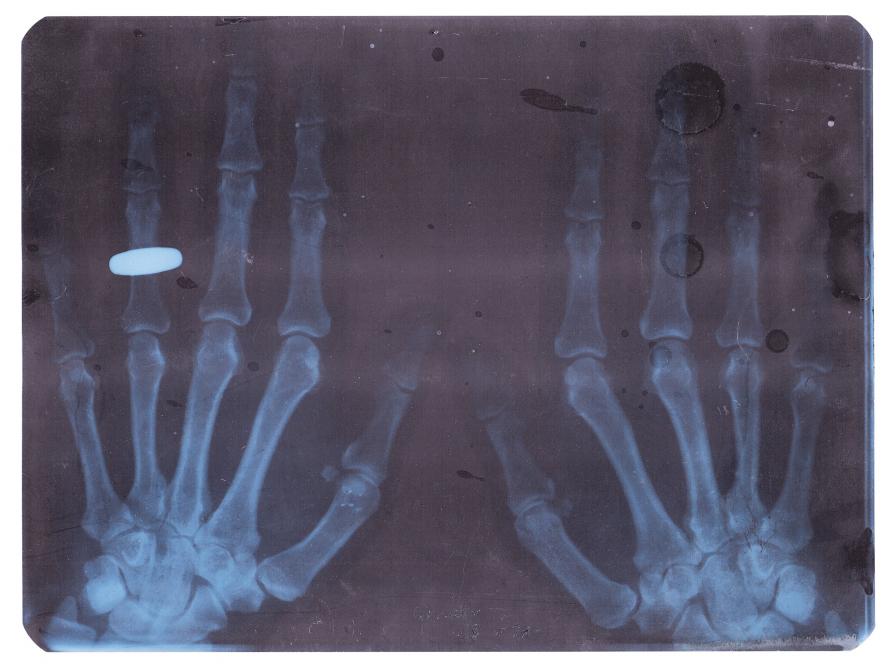

Il recupero di radiografie appartenute a un ortopedico attivo negli anni '80, permettono un'incursione attraverso il tema dell'errore, degli spazi del discorso nell'immagine e dello slittamento del senso.

La dislocazione produce delle opere simili ai rayogrammi di Man Ray o agli equivalenti di Stieglitz, continuando allo stesso tempo a parlarci della pratica vernacolare.